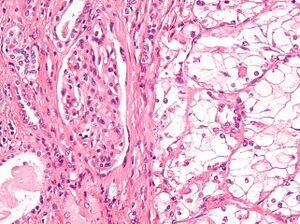

The most common type of kidney malignancy is renal cell carcinoma,[11] which is thought to originate from cells in the proximal convoluted tubule of the nephron.[9][12] Another type of kidney cancer although less common, is transitional cell cancer (TCC) or urothelial carcinoma of the renal pelvis.[13] The renal pelvis is the part of the kidney that collects urine and drains it into a tube called the ureter.[13] The cells that line the renal pelvis are called transitional cells, and are also sometimes called urothelial cells. The transitional/urothelial cells in the renal pelvis are the same type of cells that line the ureter and bladder. For this reason TCC of the renal pelvis is distinct from RCC and is thought to behave more like bladder cancer.[13] Other rare types of kidney cancers that can arise from the urothelial cells of the renal pelvis are squamous cell carcinoma and adenocarcinoma.[9]

Renal cell carcinoma has been further divided into sub-types based on histological features and genetic abnormalities. The 2004 WHO Classification of the Renal Tumors of the Adults describes these categories:[17]

- Clear cell RCC